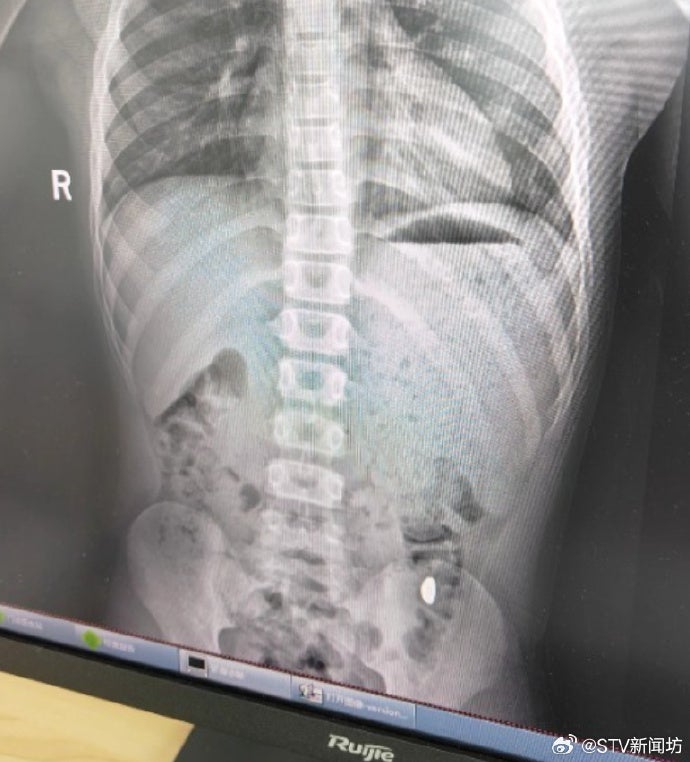

纪女士等了5天,对着儿子的大便“扒拉”了两次,还是没找到金豆,于是在10月26日带儿子到医院做检查。

儿子没出现呕吐、肚子痛等症状,但诊断结果显示他的胃中有异物。

庆幸的是,他们上午去医院,儿子下午就把金豆拉出来了。